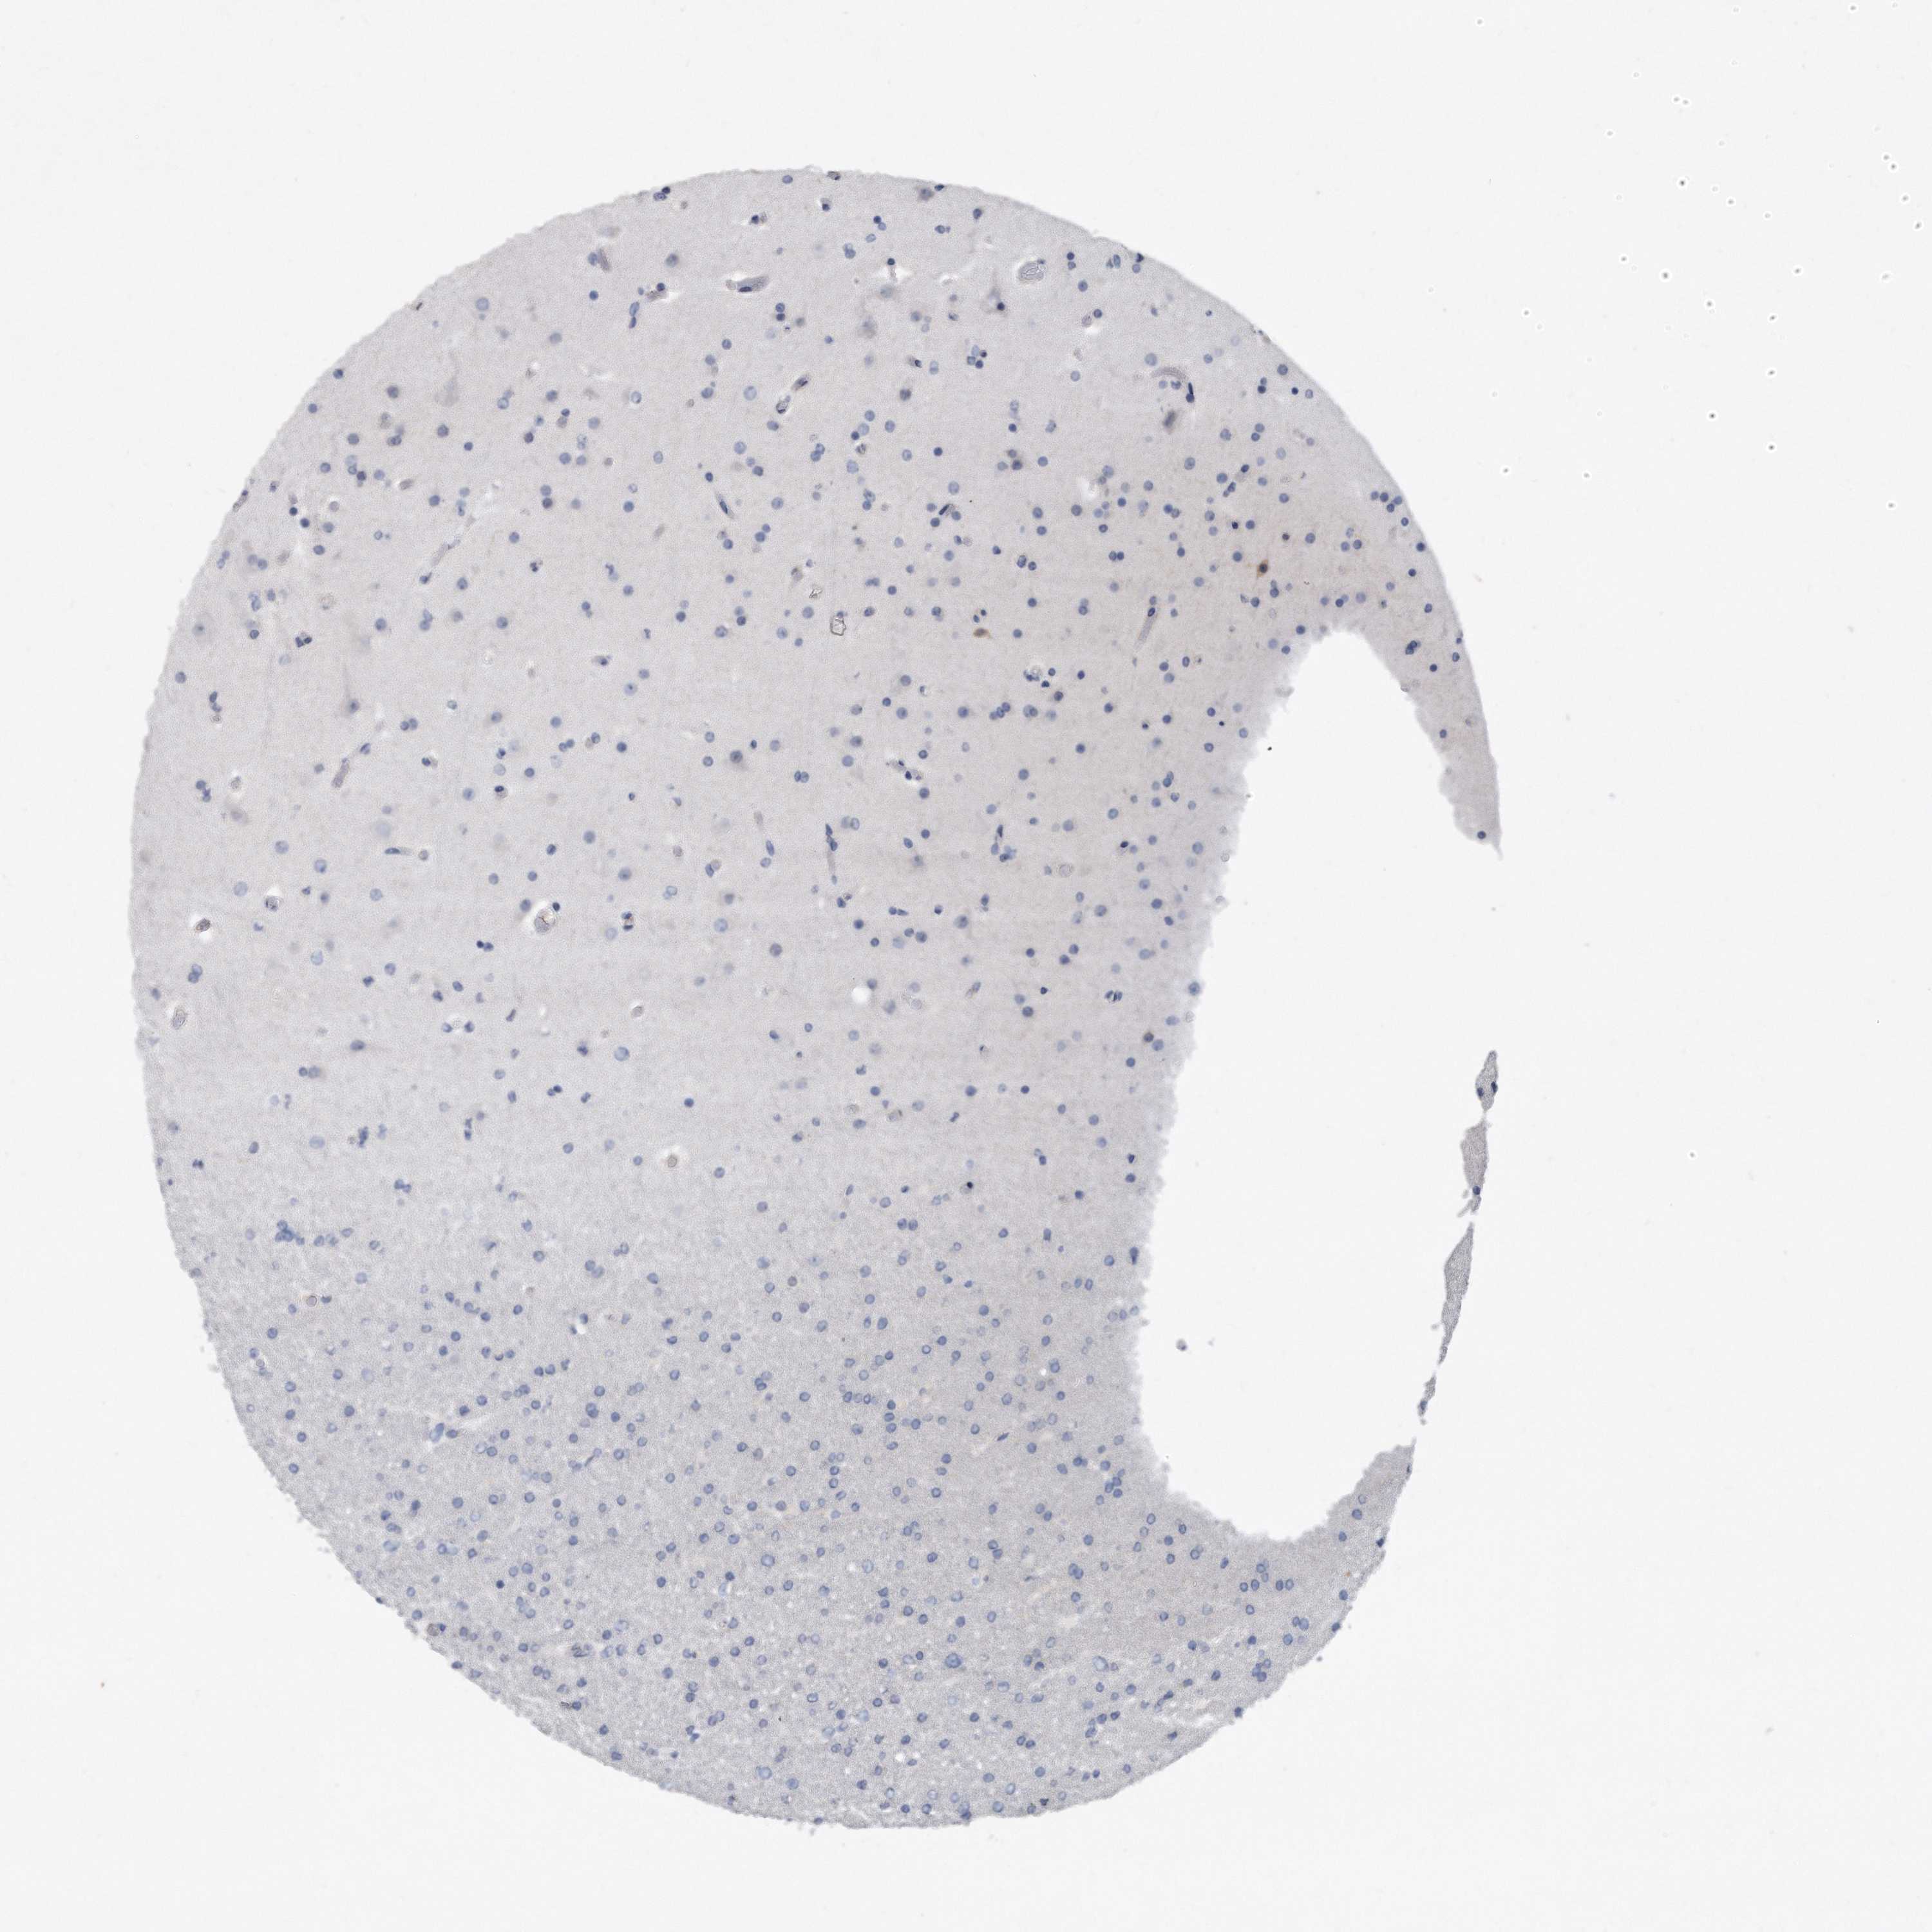

GLIOMA - Protein expressioni

A mouse-over function shows sample information and annotation data. Click on an image to view it in a full screen mode. Samples can be filtered based on level of antibody staining by selecting one or several of the following categories: high, medium, low and not detected. The assay and annotation is described here.

Note that samples used for immunohistochemistry by the Human Protein Atlas do not correspond to samples in the TCGA dataset.

Antibody stainingi

Antibody staining in the annotated cell types in the current human tissue is reported as not detected, low, medium, or high, based on conventional immunohistochemistry profiling in selected tissues. This score is based on the combination of the staining intensity and fraction of stained cells.

Each image is clickable and will lead to virtual microscopy that enables deeper exploration of all samples and also displays staining intensity scores, fraction scores and subcellular localization as well as patient and tissue information for each sample.

Antibody HPA040999

Antibody CAB032656

Staining

High

Medium

Low

Not detected

Intensity

Strong

Moderate

Weak

Negative

Quantity

>75%

75%-25%

<25%

None

Location

Nuclear

Cytoplasmic/membranous

Cytoplasmic/membranous,nuclear

Glioma, malignant, High grade

Glioma, malignant, Low grade